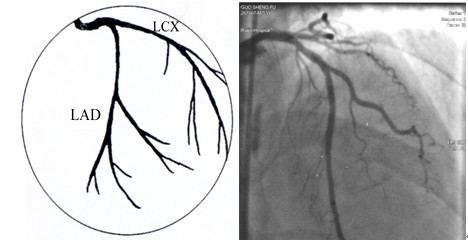

冠脉解剖与冠脉造影阅读丨影像天地

图片尺寸600x600